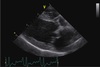

A 15-year old male castrated terrier mix presents for cough and rapid, shallow breathing. You auscult a grade IV/VI left apical holosystolic murmur and crackles throughout both lung fields. An echocardiogram is performed, shown here. **What findings are shown on this echocardiogram?** - Tricuspid valve endocarditis - Mitral valve prolapse - Pulmonic stenosis - Left ventricular concentric hypertrophy - Right ventricular concentric hypertrophy

Answer: **Mitral valve prolapse.** Explanation The correct answer is mitral valve prolapse. Note how the mitral valve bends back into the left atrium consistent with mitral valve prolapse. The valve is also thick and mitral regurgitation is likely, which fits with the heart murmur reported. The left ventricular lumen is dilated and walls appear of normal thickness, so concentric hypertrophy is not present. The pulmonic valve is not seen in this image plane. The right ventricle is not well seen either, but in the very near field, the right ventricular wall appears normal. What can be seen of the tricuspid valve does not appear to have any vegetations consistent with endocarditis. *The echocardiogram shows mitral valve prolapse, evidenced by the mitral valve bending back into the left atrium. The valve is thickened, likely causing mitral regurgitation, consistent with the reported heart murmur. The left ventricular lumen is dilated with normal wall thickness, ruling out concentric hypertrophy. The pulmonic valve and right ventricle are not visible, and the tricuspid valve lacks vegetations indicative of endocarditis.*